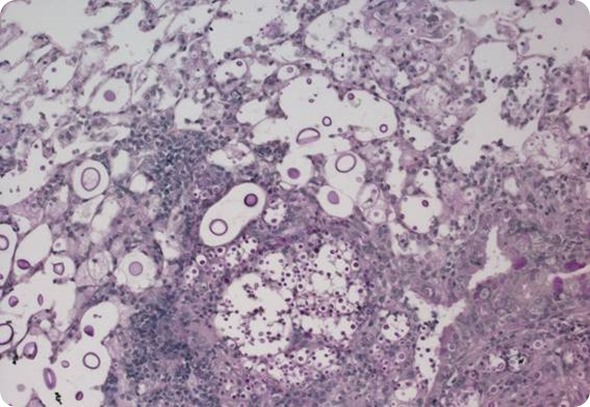

Histopathology section of lung alveolar spaces containing Cryptococcus titan and typical cells. Image courtesy of LH Okagaki and K Nielsen.